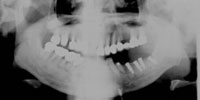

パノラマレントゲン写真

吉本歯科医院では、口内写真とパノラマレントゲンを撮影し、まずは顎の骨の状態まで詳しく確認しました。.

院長の吉本の診断は、次の3つでした。

・入れ歯では合わない、噛めないのは当たり前

・合わない入れ歯を入れているために骨がどんどん退縮していっている

・入れ歯を入れたり入れなかったりするため、歯並びがどんどん崩れだしている